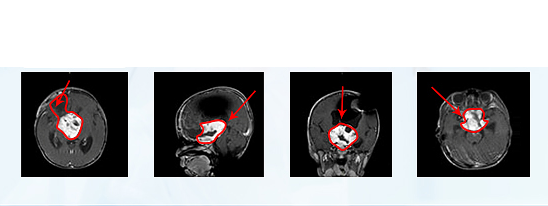

術(shù)前MR

è??è′¨??¤?????ˉ

國(guó)內(nèi)一次手術(shù)后:

??·????·′??1???è?2??????